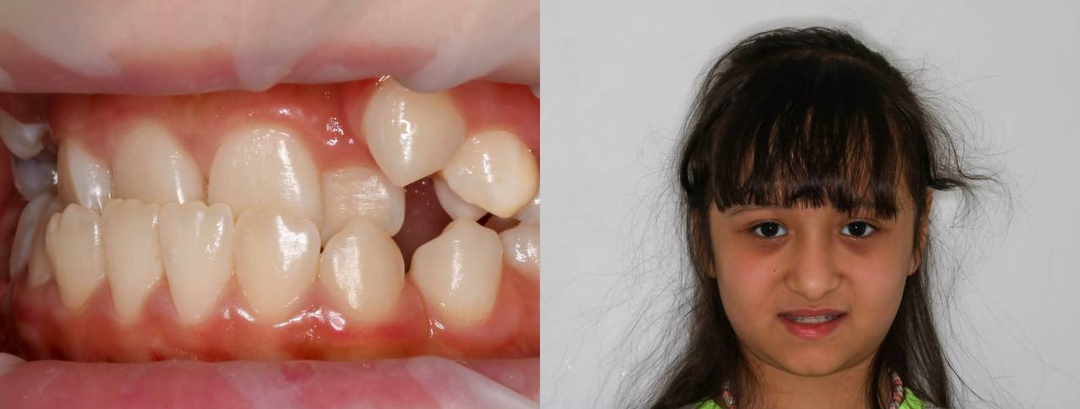

Серьезная патология прикуса у ребенка

В марте 2023 года к нам в клинику обратились родители 11-летней девочки с жалобами на большую доминирующую нижнюю челюсть и недоразвитие верхней челюсти, из-за чего у ребёнка сформировался комплекс по поводу улыбки. Обратите внимание, насколько тяжелой выглядит нижняя челюсть. У ребенка даже появился второй подбородок! А сниженная высота зубного ряда стала причиной большого объема нависания щек. На фото в анфас вы также можете заметить асимметрию лица, которая будет усугубляться с возрастом. Челюсть смещена вправо. Учитывая такой комплекс проблем, родителям было крайне важно получить профессиональное мнение — можно ли помочь их ребёнку снова полюбить свою улыбку. Давайте подробнее рассмотрим этот клинический случай и поймем, в чем был корень проблемы девочки. Внешне очень симпатичная девочка, умница и отличница, радость родителей — наша маленькая пациентка совсем не хотела улыбаться. Семья давно не была у себя на Родине, все вместе они готовились к радостной встрече, но девочка стеснял

Запрос родителей звучал просто и очень тревожно: «Ребёнок больше не улыбается. Стесняется. Над ней смеются в школе». К этому добавлялись: — трудности с жеванием, — проблемы с откусыванием пищи, — нарушение носового дыхания. Осмотр и диагностика За внешне «просто неровной улыбкой» скрывалась серьёзная функциональная проблема: — нижняя челюсть полностью перекрывала верхнюю, — выраженное смещение челюсти вбок, — формирующаяся асимметрия лица, — перегрузка мышц и сустава. Мы начали с полной диагностики и санации. Сохранили 8-е зубы, что при 3 классе прикуса удаётся далеко не всегда и требует функционального мышления, а не шаблонных решений. После большого функционального анализа (аксиография, анализ моделей в артикуляторе, виртуальный сетап и др) было проведено планирование этапов лечения пациента. ВАЖНО: лучший момент для коррекции прикуса у детей — до 7 лет. Диагностика показала 🔸 полный перекрёстный прикус во фронтальном и жевательных отделах 🔸 критически сниженную высоту нижней тр